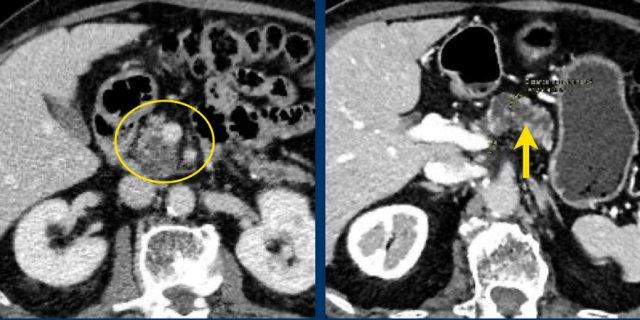

Hình ảnh CT của bệnh nhân nữ 32 tuổi với triệu chứng đau vùng thượng vị trái lan ra sau lưng.

Ghi nhận một nang lớn ở đuôi tụy có vôi hóa ngoại vi.

Có vách ngăn mờ nhạt như thấy trên hình bên trái và thành nang dày.

Có thể cần phóng to hình ảnh để quan sát rõ vách ngăn.

Có thể đưa ra chẩn đoán đặc hiệu là MCN.

Hình ảnh CT của bệnh nhân nữ 46 tuổi với triệu chứng đau bụng phải mơ hồ.

Các đặc điểm hình ảnh bao gồm:

- Nang có vách ngăn kích thước 7 cm ở đầu tụy.

- Vỏ nang nhẵn.

- Không có thùy hóa (lobulation).

- Không thông với ống tụy chính.

MRI cho thấy nang có vách ngăn ở đầu tụy kích thước 7 cm với vỏ nang nhẵn, không có thùy hóa và không thông với ống tụy chính.

Kết quả phẫu thuật xác nhận u nang tuyến nhầy độ thấp (low grade mucinous cystadenoma) có mô đệm buồng trứng (ovarian stroma).